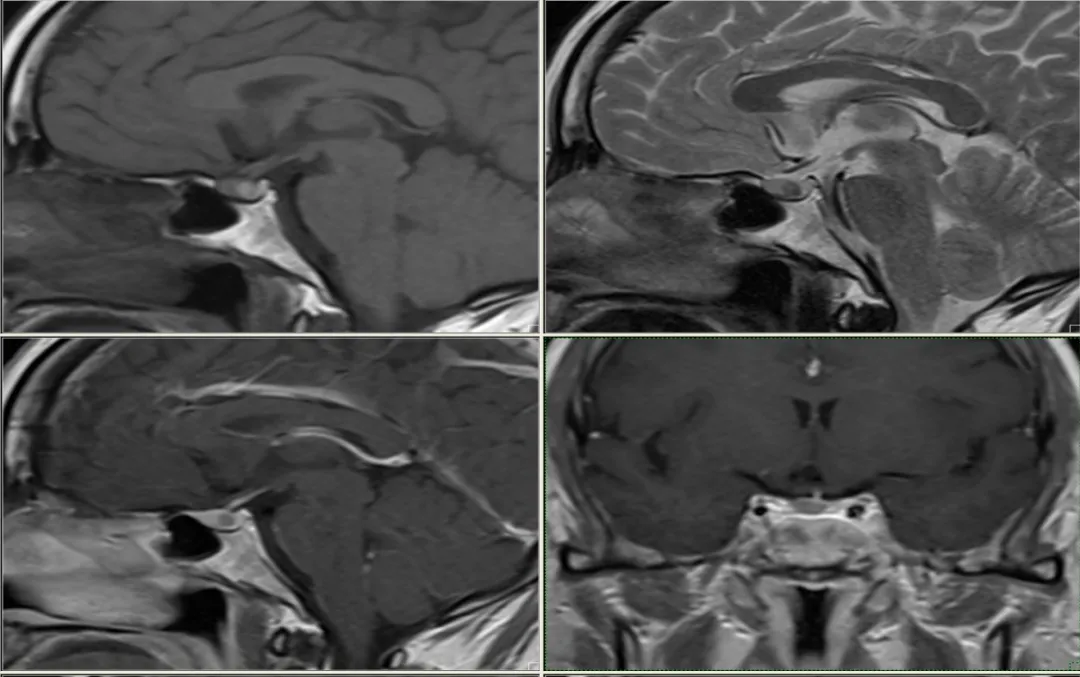

case 14:女,39 Y

看完 14 个病例,一起来认识这个表现多样的 Rathke’s囊肿

冠状位扁平,呈「蝴蝶结」状改变